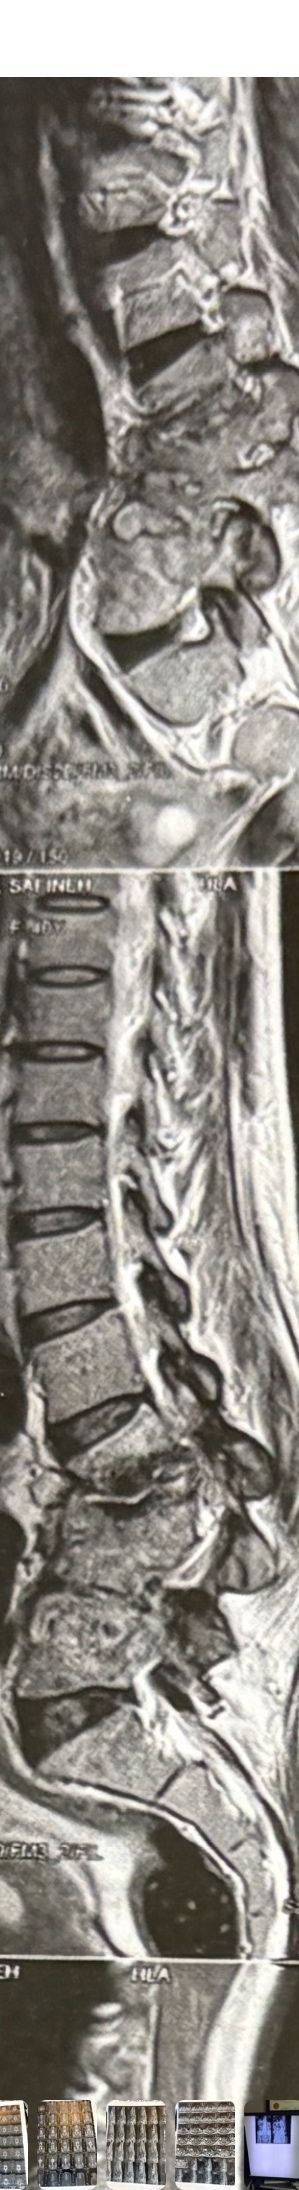

41 years old man presented to my clinic in October 2023 with acute and sever R neck pain with radicular pain to his R upper extremity along C6 dematom since 2 weeks ago. Examination didn’t show any upper motor signs. Was suggested urgent surgery

I ordered EMG/ NCV : showed mild R C6, C7 irritation without any active axonal loss

In his MRI was reported R. para R. IVF Massive extrusion. I decided to control his pain and manage this patient with reevaluation of patient every other session. For 5 sessions i just used acupuncture and laser and IFC and mild adjustments to his R. T3-T7 and mild arthosteem to above and below involved segment. Cervical adjustment considered contraindicated for this patient. From session 6th- 8th i started to use mild/gentle cervical decompression. He used soft cervical collar all the time. His pain decreased by 80 percent

I gave him cervical traction pump to be used 3-5 times per day at home for the next 3 months and i released the patient. He was evaluated every week once for one month and after that every 2 weeks. After 3 month I repeated MRI. Size of the herniated disc was reduced greater than 50 percent. Asked him to do another mri in 6 months

In general: Precise selection of the patients, examination,diagnosis, plan of management, reevaluation and treatment can be done by doctors of chiropractic for the patients with spinal disc herniation and stenosis Moreover giving reasonable time to these kind of patients under direct supervision by their chiropractic doctors can prevent unnecessary surgery. Proper selection of these kind of patients is another important fact that can be done precisely by chiropractors.

MRIs before and after proper management of this patient: